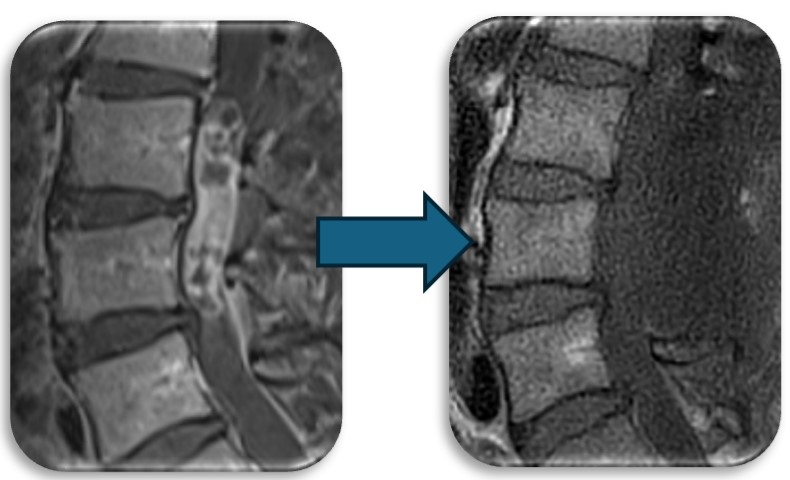

(代表例③)

腰部の脊柱管狭窄症に対して、腰の側方から徐圧し、後方から固定術(OLIF)した症例です。椎間板が摩耗していたり、不安定性がある症例、後方からの手術歴があり再手術症例に適した手術方法です。狭小化した椎間板にスペーサーを挿入(白線)する事により、脊柱管の高さを正常な状態に戻し3次元的に狭窄を改善させます。